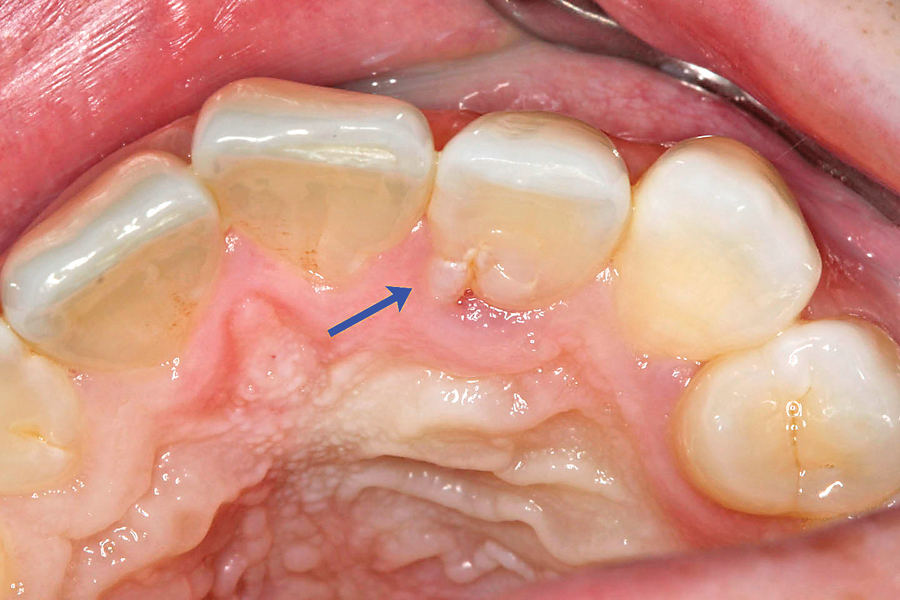

Intraoral clinical image. A trace talon cusp on the maxillary right... Extra Cusp On Lateral Incisor — lingual view of a maxillary left lateral incisor shows an enamel prominence in the lingual fossa that appears similar to a talon cusp. this may be related to the compression of the lateral incisor tooth bud caused by the adjacent ectopic canine, in turn resulting. — intraoral examination showed the presence of mixed dentition with flush. Extra Cusp On Lateral Incisor.